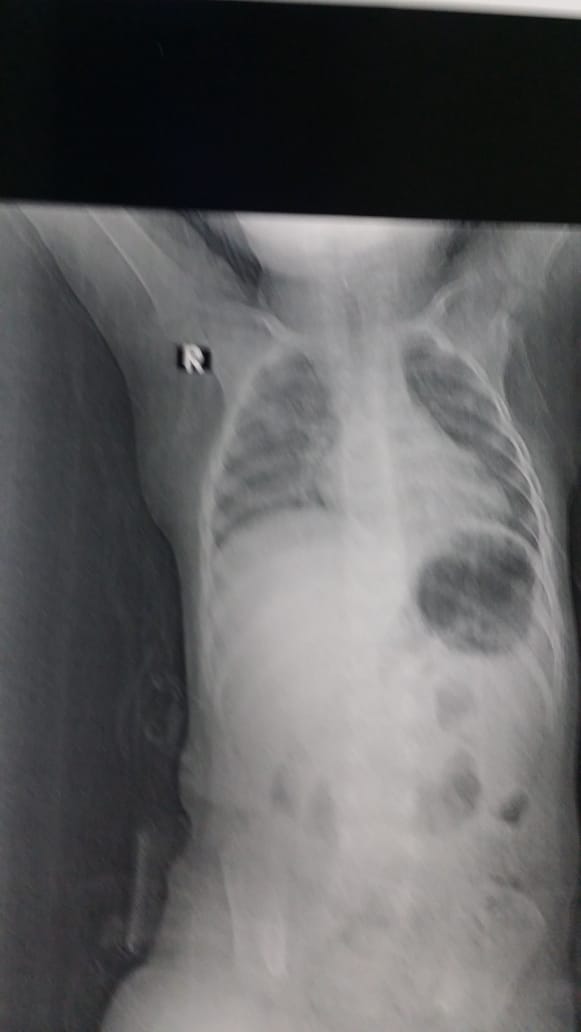

There were signs of respiratory distress (stridor). A plain chest X-ray demonstrated a radio-opaque shadow inside the trachea. A rigid bronchoscope was performed under general anesthesia, and after several attempts, a large fish bone was removed. The foreign body was found under the vocal cords, and the procedure was uneventful. The child was discharged 10 hours after bronchoscopy in a good general condition.